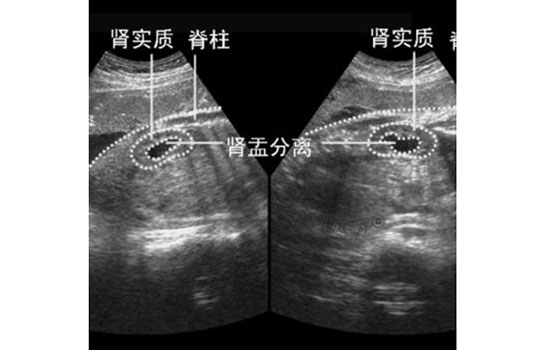

• 肾盂分离的胎儿能要吗,胎儿肾盂分离敢生吗。不少孕妈妈看到胎儿肾盂分离,就在考虑是否要终止妊娠,那么到底肾盂分离的胎儿能要吗,下面跟随小编一起详细了解了解吧~

不过孕妈妈要知道,大部分肾盂分离的胎儿都是生理性的,即肾盂分离在10毫米以内,这种情况不必担心,孕期只需要定期复查B超,胎儿完全可以顺利出生,出生后撒泡尿可能就完全没事了。

但如果胎儿胎龄大于30周,肾盂扩张≥10毫米或存在肾小盏扩张,便称为肾积水,这种情况就属于病理性的,包括上面所说的因先天性泌尿系统畸形导致的肾盂分离也是病理性的,情况严重时需要进行宫内治疗,等胎儿出生后,也要继续接受治疗。